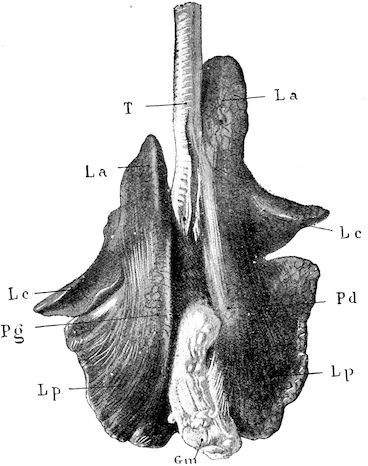

Fig. 1.—Rachitis in a young goat.

Rachitis is a disease of youth, and is common both to the human species and to all domestic animals. It is characterised by irregularities in development and by imperfect consolidation of the bones. The boundary between rachitis and osseous cachexia is difficult to define and in fact at the present moment the two diseases can scarcely be defined with exactitude. Rachitis again is often complicated with softening of the bones, disease of the limbs, arrested development, etc., but it must not be forgotten that although the irregularities in ossification and development of the skeleton are the symptoms most striking to the eye, they do not stand alone, and that from the point of view of development all the tissues, including the muscles, are more or less affected and that most of the physiological functions such as digestion and the secretion of urine are deranged.

Symptoms. The onset is absolutely insidious and the diagnosis of rachitis is never made until nutrition has long been abnormal.

This disturbance of nutrition is revealed by irregularity and abnormality in appetite, by difficulty in rising and moving about, and by the animals lying down for long periods. The subjects are feeble, sluggish and badly developed.

Next supervenes the second phase characterised by deformity of bones. This is of two kinds—deformity in the neighbourhood of joints (deformity or enlargement of the epiphyses) and deformity of the diaphyses. The former results from irregularity in ossification of the articular cartilages. The latter is followed by loss of rigidity in the bones of the limbs which, under the influence of the body weight and of muscular contraction, bend in different directions.

The bones appear of increased thickness principally towards the 6articulations. The latter are deformed, and on palpation are found to be surrounded by uneven and irregular growths.

The front limbs are distorted. In young pigs, lambs, and less frequently in foals, calves and dogs, the jaws become deformed, and mastication is rendered difficult.

The vertebral column may also be affected, and lordosis (bending downwards of the back) or skoliosis (lateral bending of the back) is somewhat frequent.

Cyphosis, or upward bending of the back, seldom occurs, and when seen, sometimes results from disease other than rachitis.

General development is always interfered with and the young creatures are generally dwarfed.

The digestive apparatus is disordered, the appetite is irregular and sometimes depraved, while indigestion, gastritis, and enteritis are not exceptional. Physiological and pathological research has shown that the quantity of phosphoric acid eliminated in twenty-four hours in a rachitic child is double the quantity passed by a healthy infant. The amount of urea in the urine (which is a criterion of nutrition, and usually varies in proportion to the amount of food ingested) is, on the contrary, diminished even when highly nitrogenous food is given, thus suggesting diminution in nutrition.

Lesions. The lesions are represented by abnormal and irregular thickening around the interarticular cartilages. The cartilage is thickened, compressible, very spongy and without regular ossification. Diffused periostitis exists principally towards the extremities of the bone. Beneath the periosteum the surface of the bone appears rough and softened. On section the medullary canals are seen to be enlarged and filled with marrow of a gelatinous character. The Haversian canals are dilated, and the entire tissue appears very vascular. Chemical analysis proves that the mineral constituents of the bone, particularly the phosphates, have diminished by one-half; the organic constituents on the other hand are increased in a similar ratio, but the ossein is abnormal. Ossification has, in a word, been incomplete.